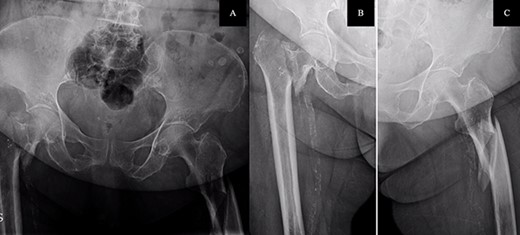

The postoperative course was satisfactory, without medical problems apart from non-complicated anemia (Hb 7.9 g/dl), solved with two units of red blood. On the first postoperative day, a radiographic control was completed (Fig. 3) and started early ambulation assisted by physiotherapists. On day twelve, she was transferred to a rehabilitation hospital. Outpatient follow-up visits evolving reasonably well. In the 6-month and 1-year check-up, the consolidation of the fracture was observed in the radiographic study (Fig. 4). No surgical wound problems, infections, or limping were identified. Anti-osteoporotic drug treatment was implemented along with an emphasis on a healthy diet with adequate protein intake and supplementation with calcium and vitamin D.

Radiological evaluation on follow-up at 1 year. Pelvis anteroposterior radiograph view showing signs of consolidation, without evidence of loss of reduction or implant failure.